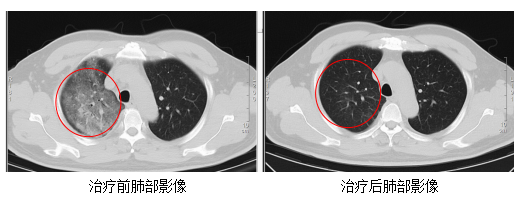

胸部CT成果骄气,他的双肺存在大面积的炎症病变,当场被转至感染科收受治愈。

过程治愈,顾先生的发烧、咳嗽、胸闷等症状逐步缓解,肺部炎症显著改善,现已康复出院。